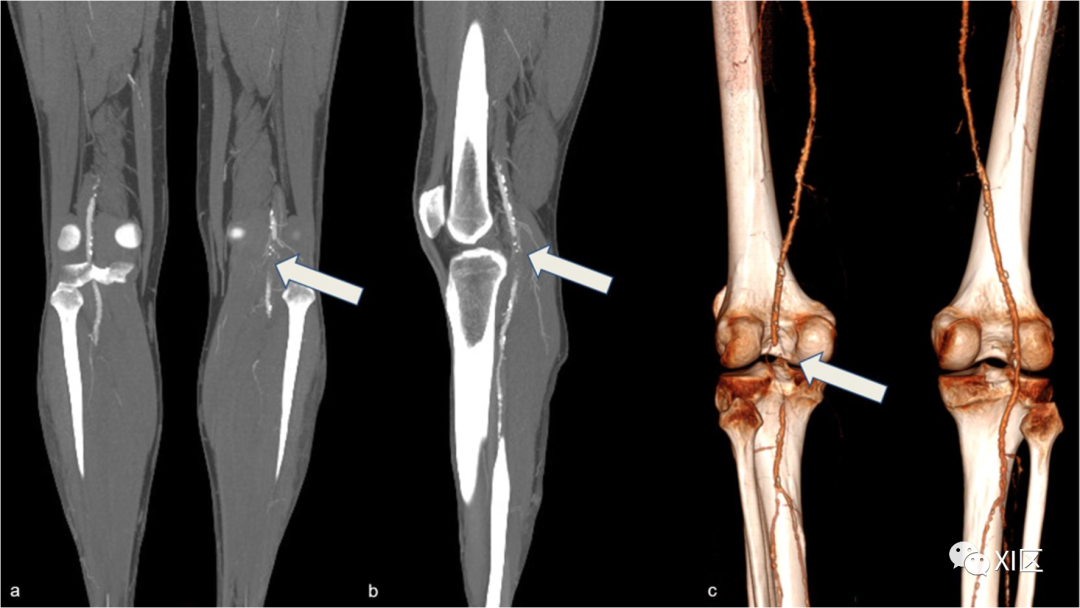

患者通常有跛行病史,其他血管的CTA也可见动脉粥样硬化异常。8%的腘动脉瘤患者可能出现ALI(图5)。

腘动脉瘤包括腘动脉的局灶性扩张,其直径大于对侧腘动脉或股浅动脉的直径,在高达75%的病例中为双侧受累(图6)。

图6 双侧腘动脉瘤。75岁男子出现左室缺血症状。VRT重建显示双侧腘动脉瘤(a)。右侧动脉瘤的CPR重建显示了巨大的贴壁血栓。c 左侧动脉瘤的CPR重建显示动脉瘤的很大一部分没有被造影剂填充。

与这些动脉瘤相关的并发症包括血栓形成、壁血栓栓塞和破裂。CTA可以检测动脉瘤的特征,包括口径、颅尾延伸、壁血栓的形态、流出的解剖结构,并确定不能用DSA评估的造影剂填充的腔内部分,以便进行正确的治疗管理。